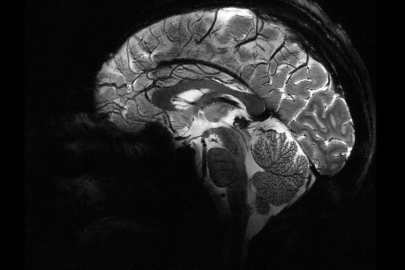

İngiltere’de yapılan bir araştırmaya göre, COVID-19 döneminde insanların beyinleri 2020 öncesine kıyasla ortalama 5,5 ay daha hızlı yaşlandı. Üstelik bu artış, COVID geçirmeyenlerde de görüldü. Uzmanlar değişimlerin tersine dönebileceğini söylüyor.

Nottingham Üniversitesi’nden bilim insanları, UK Biobank’ta yer alan 15 binden fazla yetişkinin verileriyle sağlıklı beyin yaşlanmasını tanıyan bir yapay zekâ modeli geliştirdi. Model, pandemiden önce tarananlarla, önce ve pandemi sırasında taranan iki grubun beyin yaşlarını karşılaştırdı.

Science Alert'in haberine göre, Araştırmaya göre, pandemi sürecinde insan beyninin yaşlanma hızı ortalama 5,5 ay öne çekildi.

Çalışmayı yürüten nörolog Ali-Reza Mohammadi-Nejad, “COVID geçirmeyenlerde bile belirgin artış gördük. İzolasyon ve belirsizlik gibi faktörler beyin sağlığını etkiledi” dedi.